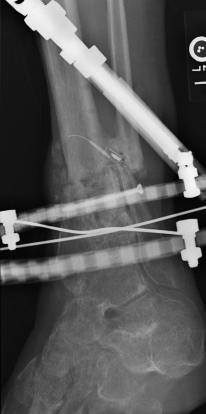

Postoperative (13th) images of left ankle

The image(s) displayed here were created following Liam's 13th surgery which was performed by Dr. Saunders. After a few hiccups getting

the surgery scheduled, Liam spent most of the September 13th afternoon in his 13th surgery. ;-) The surgery lasted about 5 hours and according

to the doctor, it was a good surgery. The 1st photo shows the new frame bracing that holds Liam's ankle together. The next series of photos show

various angles of the ankle and the rods that go from the frame into and through the left ankle. There was some concern that the swelling would

burst and allow for infection. Looks like we are now past that concern. Liam is still on antibiotics to ward of potential infection. The flesh

images show how the skin reacts to having the leg adjusted by the brace. The doctor has had to cut the skin to allow the rods to move freely.